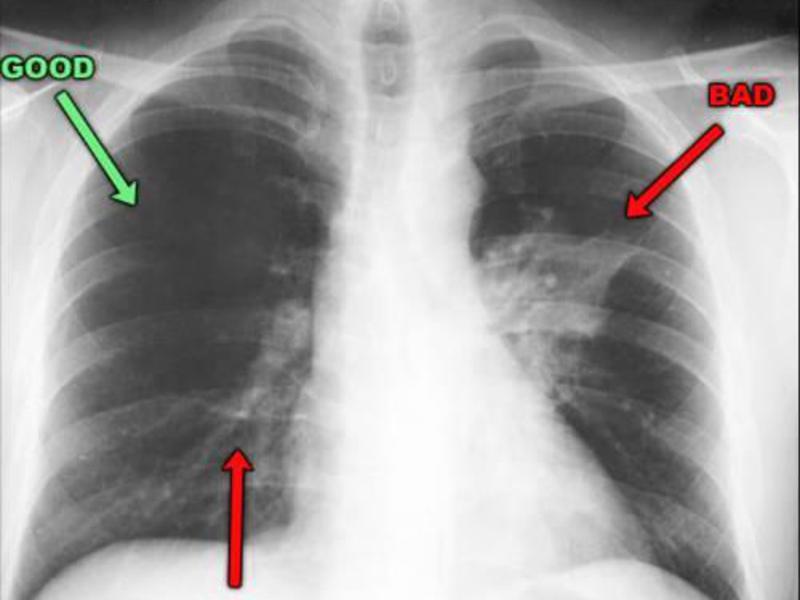

После проведения рентгенографии снимки должен изучить специалист, и на основе полученных данных и результатов других исследований сделать соответствующие выводы и поставить диагноз. В норме легкие и бронхи человека выглядят следующим образом:

- легочные доли имеют одинаковый, равномерный черный оттенок;

- в районе сердца наблюдается белый просвет;

- ребра и ключицы серые, с привычными очертаниями;

- купола диафрагмы белого цвета;

- позвоночный столб расположен в центре.

Признаки пневмонии на рентгеновском снимке во многом зависят от формы заболевания и его стадии, а также от локализации патологического процесса. Если исследование показало признаки пневмонии, необходимо как можно скорее приступить к лечению – запущенный патологический процесс опасен не только для здоровья, но и для жизни человека.

Первый признак пневмонии на рентгеновском снимке – появление очагов затемнения с неровными контурами в разных частях легкого, которые могут иметь разный размер, от 3-4-х до 12 мм.

Тени различают по внешнему виду (круглые, овальные кольцевидные) и интенсивности окраски – чем темнее пятно, тем сильнее выражен патологический процесс.

При поражении лимфатических узлов и нарушении кровоснабжения органа могут наблюдаться изменения корней легких, а если болезнь затронула плевру – нарушение в рисунке куполов диафрагмы. В остальном проявления пневмонии зависят от стадии, формы и клинических особенностей заболевания: